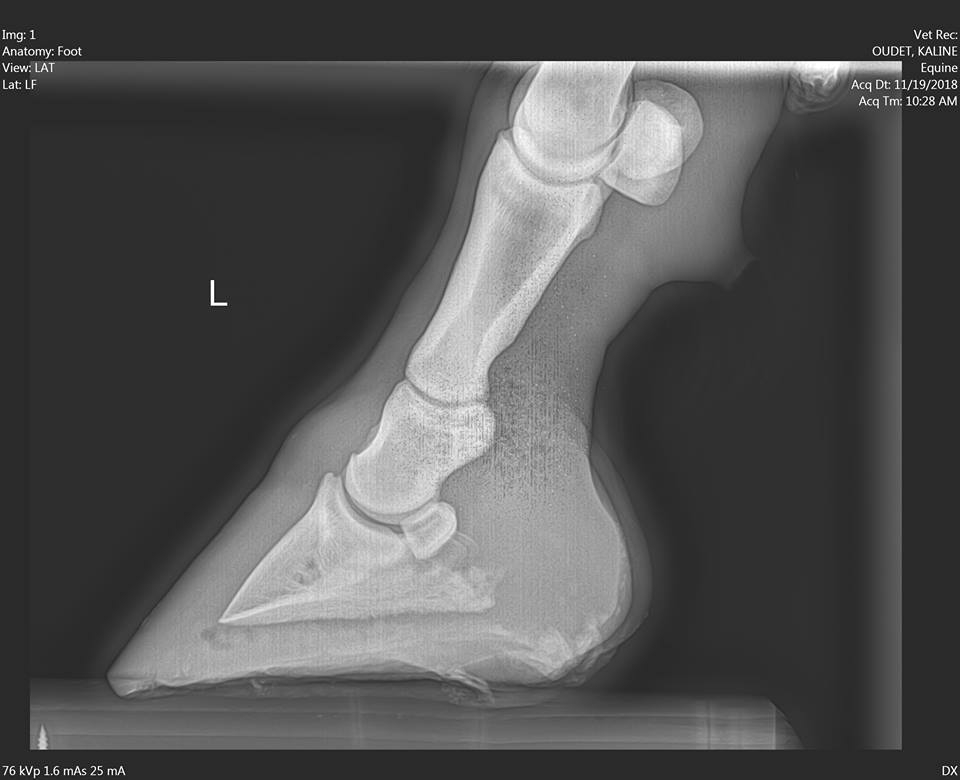

| Dire merci | Bon ben j'ai profité des ondes magiques du forum, ça a percé aujourd'hui, de façon inatendu dans la ligne blanche On avait affiné la sole là où le sabot était le plus douloureux (à la seule pression des doigts). Mon podologue était d'avis de percer à cet endroit. La véto préférait attendre que l'animalintex fasse son travail, plutôt que de fragiliser le pied, vu l'épaisseur de sole à traverser. C'est du cas par cas, je pense pas que d'ouvrir systématiquement la boite cornée se justifie quand même... Radio ![]() Cavité aujourd'hui ![]() |

| Dire merci | Contente pour toi elle doit être soulagee ! Question radio : l'abcès c'est le point noir qu'on voit au bout de la P3 ? |

| Dire merci | Oui c'est la tache un peu diffuse juste sous la pointe ![]() |